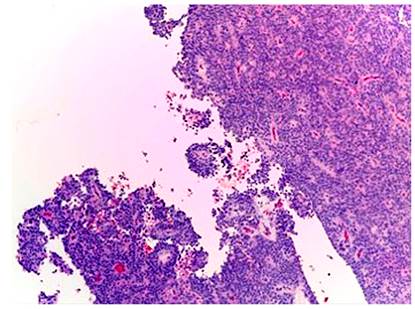

Histológicamente, todos los casos presentaron un patrón sólido y pseudopapilar, con células de apariencia epitelioide; un caso presentó células de aspecto sarcomatoide y otros dos con presencia de células gigantes multinucleadas. El pleomorfismo nuclear estuvo ausente o fue leve en la mayoría, solo hubo un caso con pleomorfismo grave y presencia de mitosis atípicas, el cual corresponde a una paciente femenina de 56 años. En el resto de tumores, la actividad mitótica fue escasa o nula sin figuras atípicas (Figuras 1,2, 3,4,5,6,7,8 y9).

El tumor sólido pseudopapilar afecta principalmente a mujeres jóvenes, con una relación 9:1, se presenta con síntomas abdominales inespecíficos, como abdomen agudo en caso de ruptura de la lesión por trauma o como hallazgo incidental en las imágenes radiológicas1,4. En La tomografía axial computarizada (TAC) y resonancia magnética (RM) de abdomen se observa una masa bien encapsulada con densidades o intensidades heterogéneas, lo que refleja degeneración quística y hemorragia dentro del tumor5. Macroscópicamente, alcanzan medidas de 10 cm o más; son masas bien circunscritas, sólidas y quísticas; las áreas sólidas tienen una consistencia friable y las áreas quísticas presentan necrosis y hemorragia5-7. Microscópicamente, tienen una arquitectura sólida y pseudopapilar alrededor de los vasos sanguíneos delgados8. Las células neoplásicas son discohesivas, de aspecto epitelioide con núcleos redondos y hendiduras, no hay atipia nuclear importante y las mitosis son infrecuentes. Las células tienden a alejarse de los vasos sanguíneos y se degeneran, lo que produce las extensas áreas de necrosis; las células que se mantienen alrededor de los tallos fibrovasculares forman una o múltiples capas que dan el aspecto pseudopapilar característico de la lesión. El estroma puede tener grados variables de hialinización. Pueden existir pequeños grupos de histiocitos epitelioides que acompañan la lesión1,4-8.